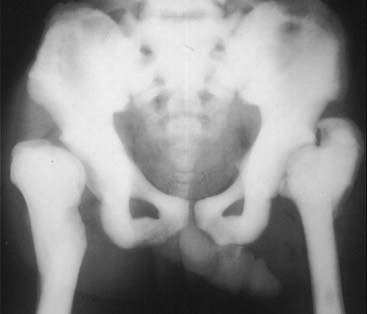

image Osteopetrosis (also called marble bone disease for obvious reasons) is a rare hereditary defect in osteoclastic activity that ultimately results in an increase in bone density affecting the entire skeleton (Fig. 21-5).

image

Figure 21-5 Osteopetrosis (marble bone disease).

A frontal view of the pelvis demonstrates diffuse sclerosis of the bones in this 22-year-old patient with osteopetrosis, a rare defect in osteoclastic activity that results in an increase in bone density. Although the bones are dense, they are mechanically inferior to normal bone and subject to pathologic fractures. In the infantile form of this disease, the defective osseous material can replace normal bone marrow leading to anemia, thrombocytopenia, and leukopenia (pancytopenia).